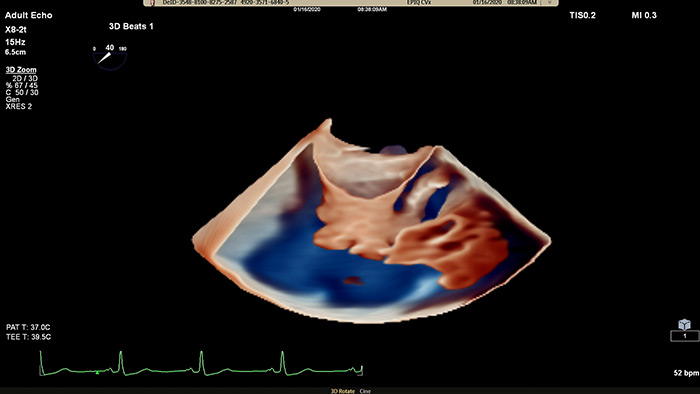

View enhanced visualizations of structures and flow with TrueVue Color